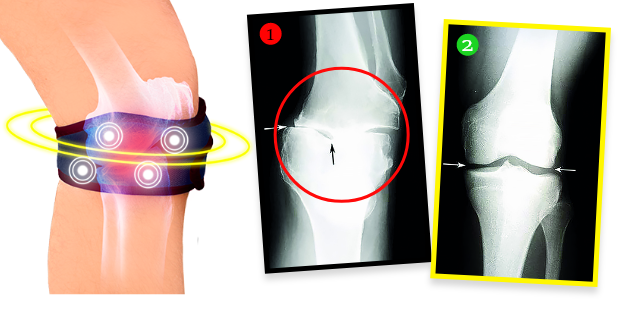

Pani Helena po ošetrení urobila röntgen a ukázalo sa, že degeneratívne zmeny v kolene sa úplne zvrátili! Doktor bol zarazený – nevedel, čo povedať. A fakty sú také, že vďaka biomagnetickému pásu sa nielenže stav kolena pani Heleny prestal zhoršovať. Chrupavkové tkanivo a jemné štruktúry v kĺbe sa zregenerovali a koleno sa vrátilo do plnej funkčnosti. Pás vyžaruje prirodzené a bezpečné biomagnetické pole, ktoré preniká do najhlbších tkanív kĺbu, vyživuje a regeneruje chrupavku, obnovuje jej elasticitu a tiež stimuluje tvorbu synoviálnej tekutiny, ktorá tlmí a chráni pred bolestivým trením pri pohybe. Je to úplne neinvazívna a bezpečná terapia.